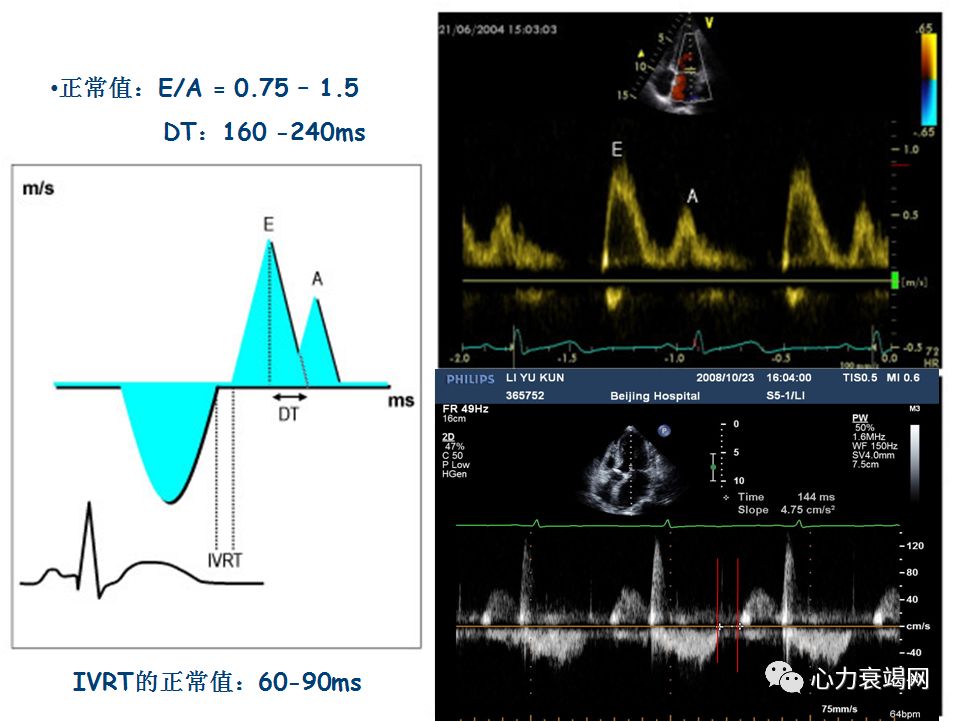

检测前提:窦性心律,连接ECG获得清晰肺静脉血流频谱

检测指标:S/D比值,PV频谱Ar时间

取心尖四腔切面,启动CDFI并调整M型取样线通过二尖瓣口至心尖使之与舒张期充盈血流平行,然后启动M型成像,在窦性心律者显示两个与E和A相关彩色血流,测量舒张早期充盈血流出现彩色混叠颜色变化前缘向心尖方向延伸4cm处的斜率。

E / Vp>1.5 时 LA 压力增高。

AMI 后E / Vp<1.5者的预后明显好于E/ Vp≥1.5者。

有报道E/ Vp预测AMI 后发生心衰及死亡的价值优于EF。